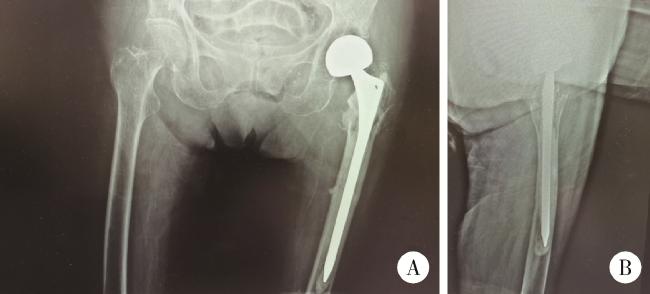

图1 患者第一次入院前髋关节X线片

Figure 1 Hip joint X-ray of patient before initial admission

A, radiographic examinations, including X-ray imaging of anteroposterior view of hips; B, lateral view of left hip, indicate the presence of an intertrochanteric fracture in the left femur.